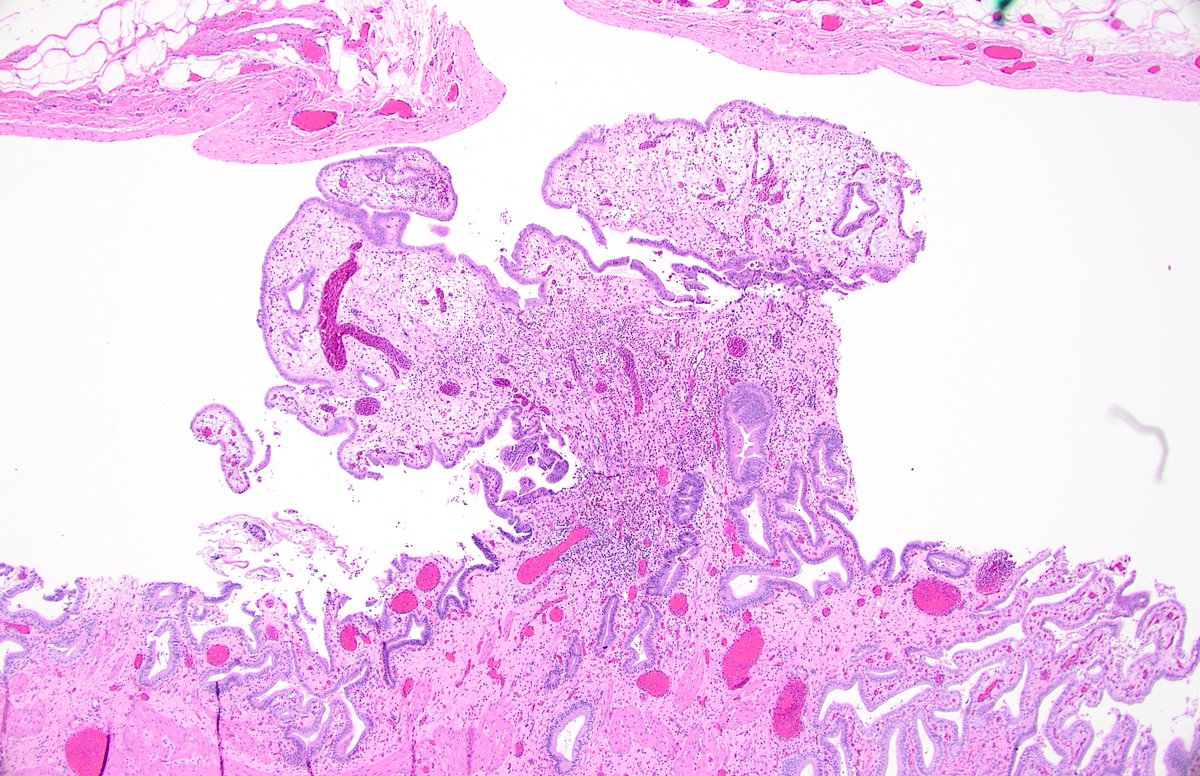

@forthejon @et565 On morphology I would have gone for HG dysplastic naevus. PRAME and molecular seem to point in the same direction here and what you have said is v reasonable. Management is the same - wider excision.

#WhatsNewInDermpath Utilizing PRAME expression and a meta-analytic framework for iSALT to explore atypical late-onset nevi of the elderly and their relationship with lentiginous and nested nevoid melanomas journals.lww.com/amjdermatopath…